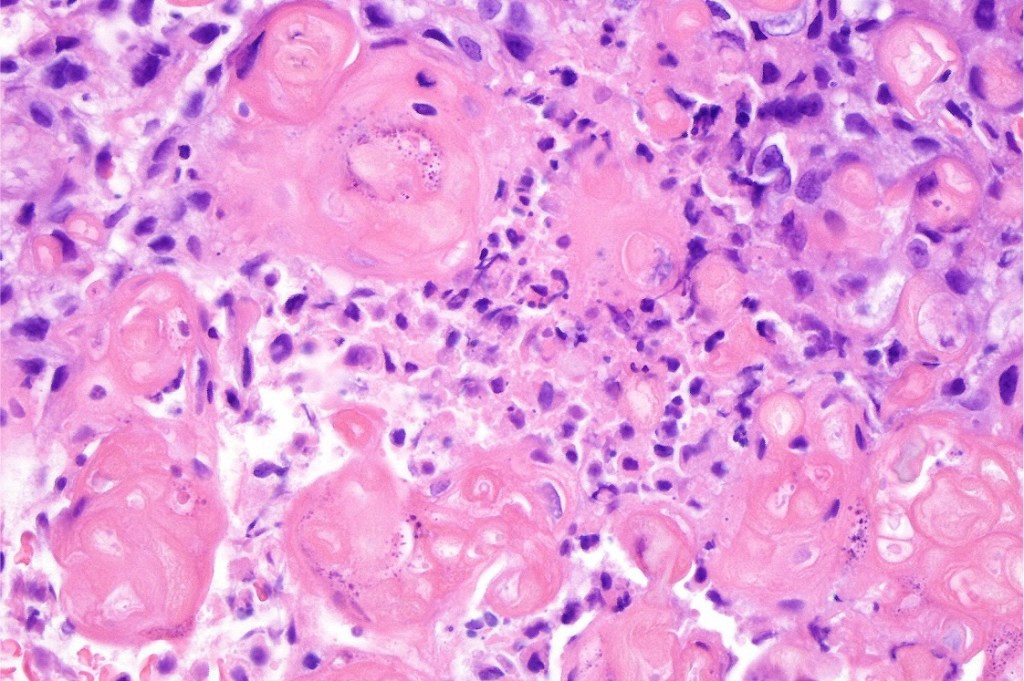

Histological features

•Well circumscribed nodular or multinodular growth pattern

•Admixture of basaloid matrical, supramatricial & eosinophilic shadow cells with dendritic melanocytes. The ghost cell change is distinctive affecting individual cells with preservation of their cytological detail rather than the en masse change typical of pilomatricoma

•Variable pleomorphism and mitotic activity affecting the matrical cells